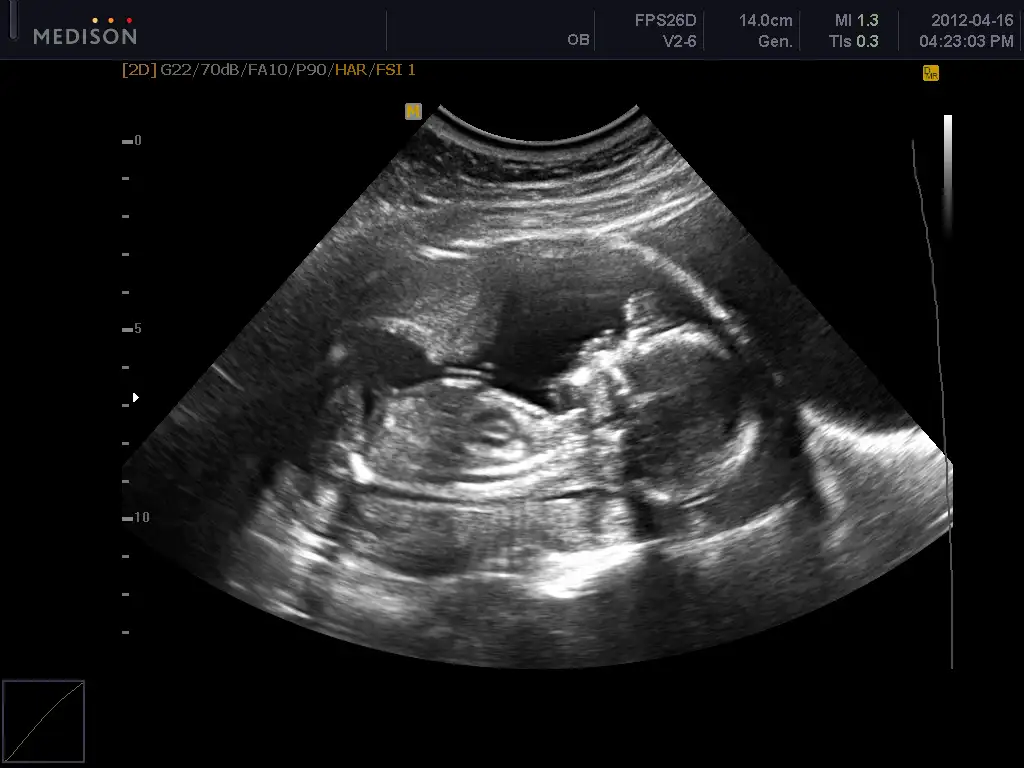

bende bugün bebeğimi ayrıntılı ultrason için 4 boyutluda görmey gititim çok belli yüzü

boydan veremem artık 5 ay bitti boy alınmıyor dedi

seninde son boydan dotoların :) bundan sonra profilden yüzden veriyorlar

bu arada bebekelr lastik gibiymiş doktor bebğimin ayağının alnında olduğunu söyledi :53:

ama ssaolsun bak bura ayak demedi sadece söyled, ben ekrandan baktım ama anlamadım

buda benim kzıım